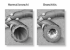

Появившаяся мокрота в горле является лишь следствием сложных процессов, обусловленных нарушением функционирования дыхательной и сердечнососудистой систем. Поток воздуха, проходя через верхние дыхательные пути перед тем как попасть в легкие должен нагреться и очиститься от пыли и бактерий. Микрочастицы грязи задерживаются специальным реснитчатым эпителием и выводятся впоследствии через ротовую и носовую полость в виде слизи.

Если вместе с воздушной струей человек вдыхает сигаретный дым, деятельность ресничек угнетается и слизь оседает в полости легких, затрудняя дыхание и становясь очагом воспалительного процесса. Кроме того, ядовитые составляющие табачного дыма являются мощными канцерогенами, что самым негативным образом сказывается на состоянии сердечной мышцы и сосудов, патология которых также проявляется мокротовидными выделениями.